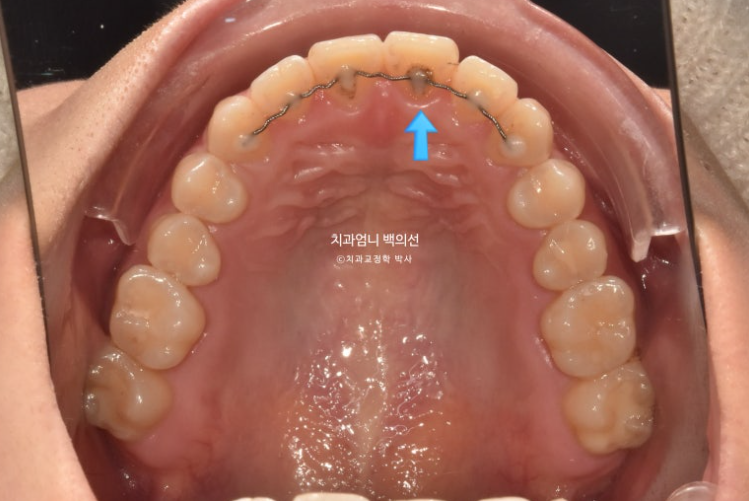

위 앞니 하나가 올라간 것은 철사가 떨어져서가 맞습니다.

파란 화살표 접착제가 까맣게 보이는 것은 접착제가 치아와 분리된 상태이기 때문입니다.

하지만 아래는 철사가 떨어진 부분도 없고 떨어진적도 없습니다. 철사가 붙어 있는 상태에서 철사 자체의 변형으로 치열이 틀어지는 경우가 있습니다. 와이어신드롬 이라고 합니다.

사용한 부분교정용 장치는 MTA 미니튜브 이고 고무줄 처방이 함께 들어갔습니다.